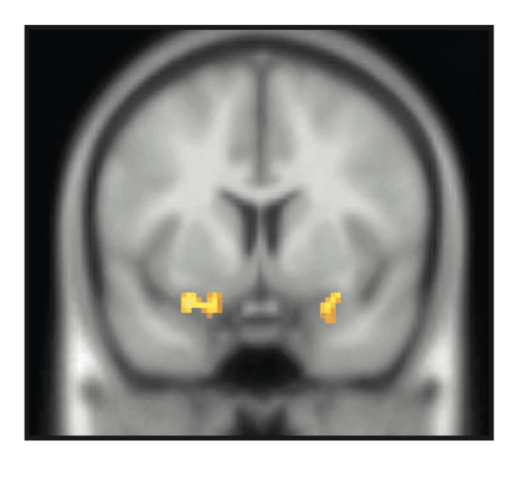

While these results demonstrate that there is a correlation between the roughness of screams and a listener’s fearful response to them, it doesn’t quite explain why screams make our skin crawl. To begin to answer this question, the NYU researchers looked to brain imaging using fMRI to measure blood flow to different areas of the brain when participants heard screams versus neutrally spoken words and alarms versus neutral sounds. Intriguingly, while neutral speech is processed through the typical sound processing pathways that start in the inner ear and make their way to the auditory cortex, screams and alarm sounds with increased roughness cause an increase in blood flow to the amygdala, a known emotional processing center in the brain [2]. The amygdala has long been implicated in humans and animals in a variety of behaviors, but is best known for its role in fear processing and fear learning [3]. The fact that the amygdala is active while listening to screams and not other vocal sounds suggests that’s the place in the brain where the perception of a shriek and the resulting unsettling fear may come together.

fMRI imaging shows increased blood flow to the amygdala in human participants listening to screams as compared to neutral sounds. From [2].